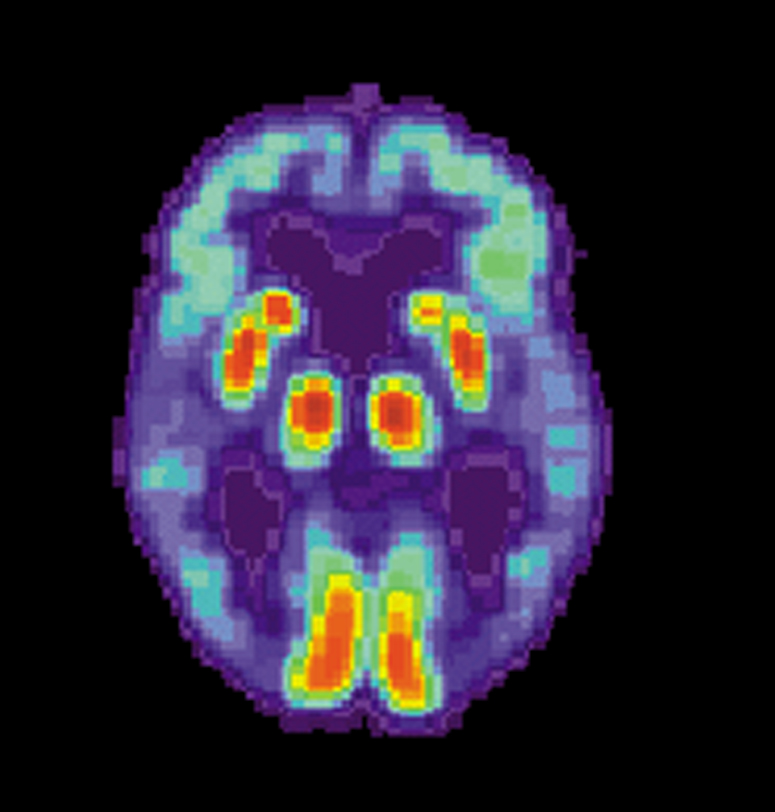

ПЭТ мозга с болезнью Альцгеймера ПЭТ мозга с болезнью Альцгеймера Фото: US National Institute on Aging, Alzheimer's Disease Education and Referral Center/wikimedia.org